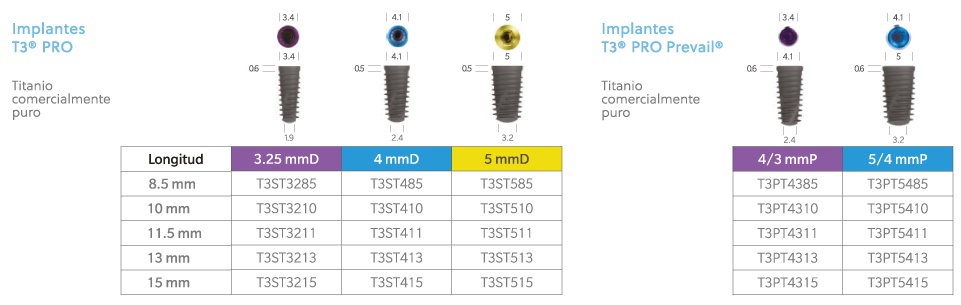

El implante T3® PRO de ZimVie® es la versión de nueva generación del implante cónico, diseñado para ofrecer una alta estabilidad primaria y posibilidad de función inmediata, reduciendo los tiempos de tratamiento sin sacrificar los resultados estéticos ni la salud ósea a largo plazo.

Su ingeniería incluye un núcleo totalmente cónico con roscado progresivamente más profundo hacia el ápice, lo que permite un contacto inicial hueso-implante alto y una inserción controlada. Además, cuenta con una superficie híbrida contemporánea, destinada a favorecer la osteointegración y mantener el nivel óseo periimplantario.

El sistema conserva la conexión interna Certain® compatible con la tecnología SureSeal™ y “Platform Switching”, lo que asegura un sello fuerte entre implante y pilar. Esto ayuda a minimizar micromovimientos o filtraciones, factores importantes para la durabilidad y salud del implante.

Prevail® Platfrom Switching®